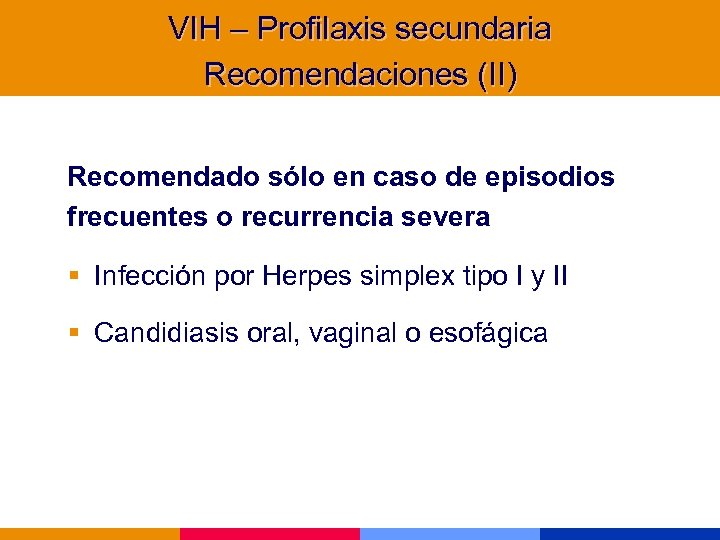

VIH – Profilaxis secundaria Recomendaciones (II) Recomendado sólo en caso de episodios frecuentes o recurrencia severa § Infección por Herpes simplex tipo I y II § Candidiasis oral, vaginal o esofágica

VIH – Profilaxis secundaria Recomendaciones (II) Recomendado sólo en caso de episodios frecuentes o recurrencia severa § Infección por Herpes simplex tipo I y II § Candidiasis oral, vaginal o esofágica